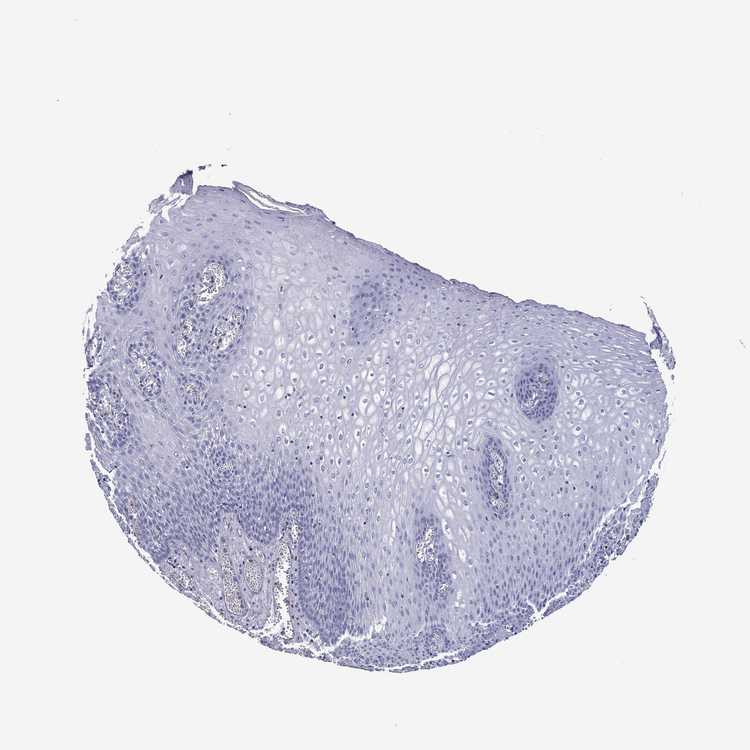

TISSUE PRIMARY DATA ESOPHAGUS Show tissue menu

Esophagus

ESOPHAGUS - Antibody stainingi

Antibody staining in the annotated cell types in the current human tissue is reported as not detected, low, medium, or high, based on conventional immunohistochemistry profiling in selected tissues. This score is based on the combination of the staining intensity and fraction of stained cells.

Each image is clickable and will lead to virtual microscopy that enables deeper exploration of all samples and also displays staining intensity scores, fraction scores and subcellular localization as well as patient and tissue information for each sample.

Antibody HPA045827Antibody HPA072480

Squamous epithelial cells Not detectedNot detected